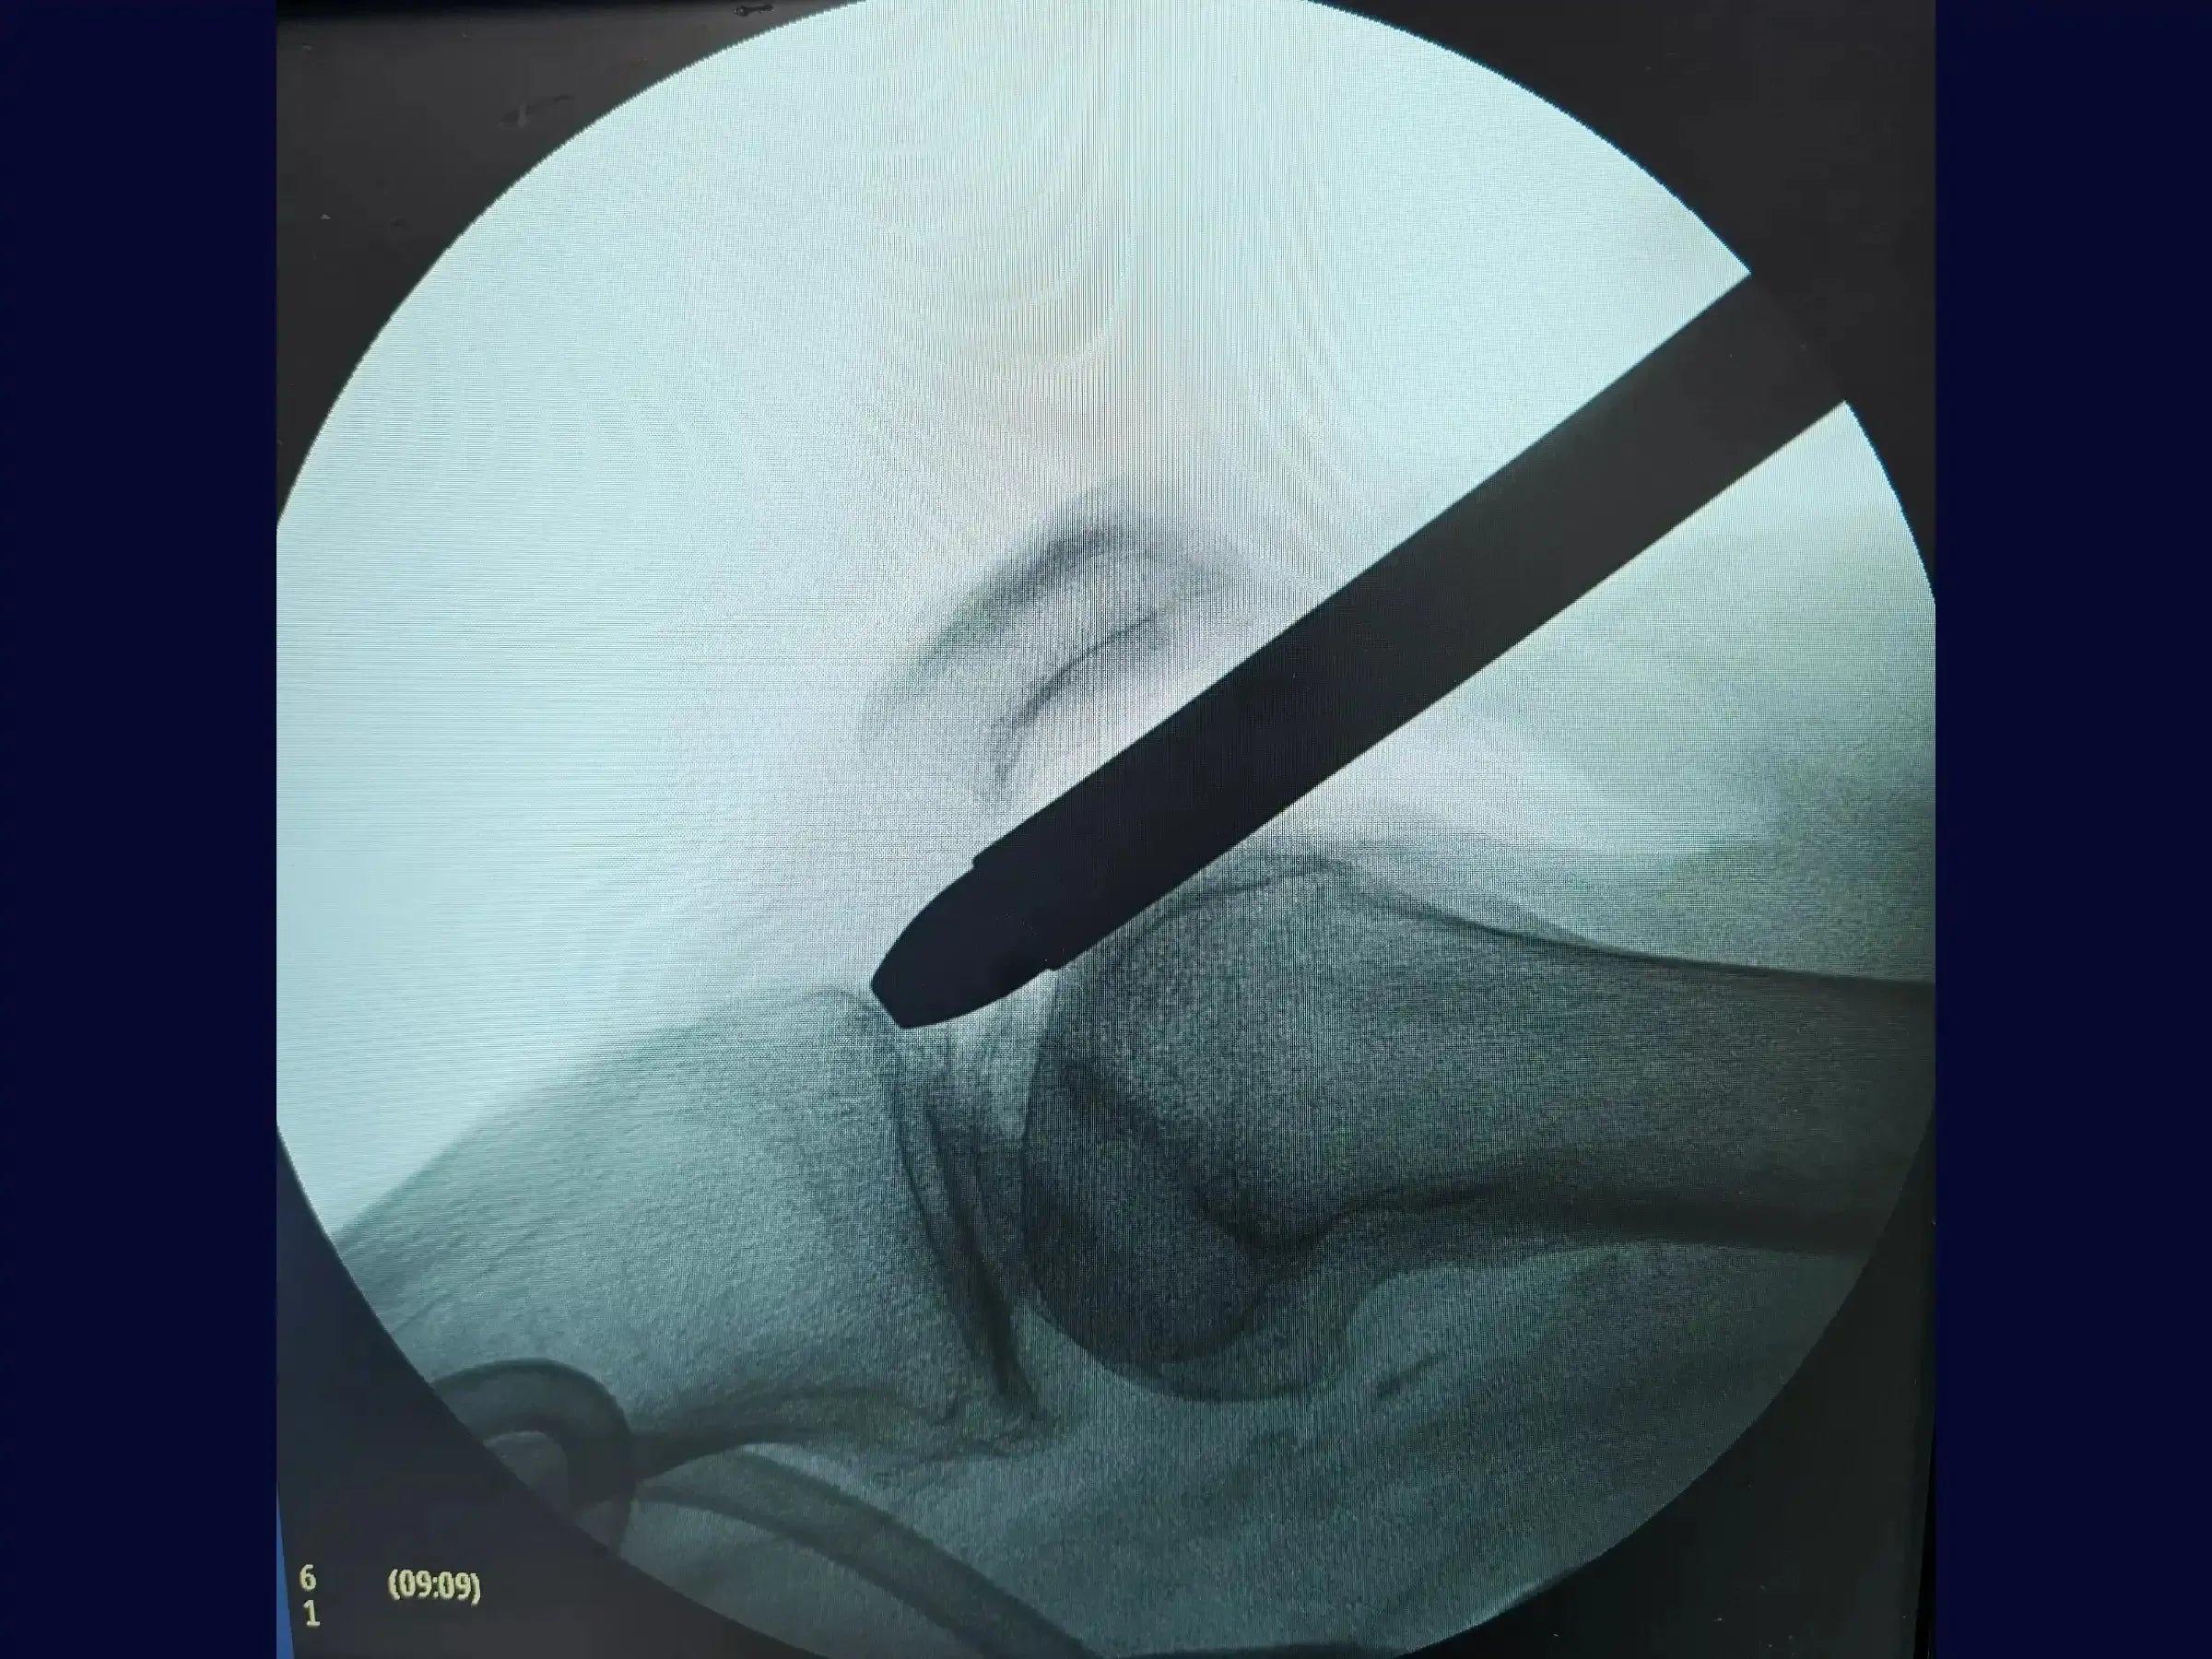

- Redução e Inserção do Fio Guia: Metodologia para redução percutânea com pinça, com progressão do fio guia olivado e verificação de sua centralização nas incidências AP e perfil, visando o centro do tornozelo.